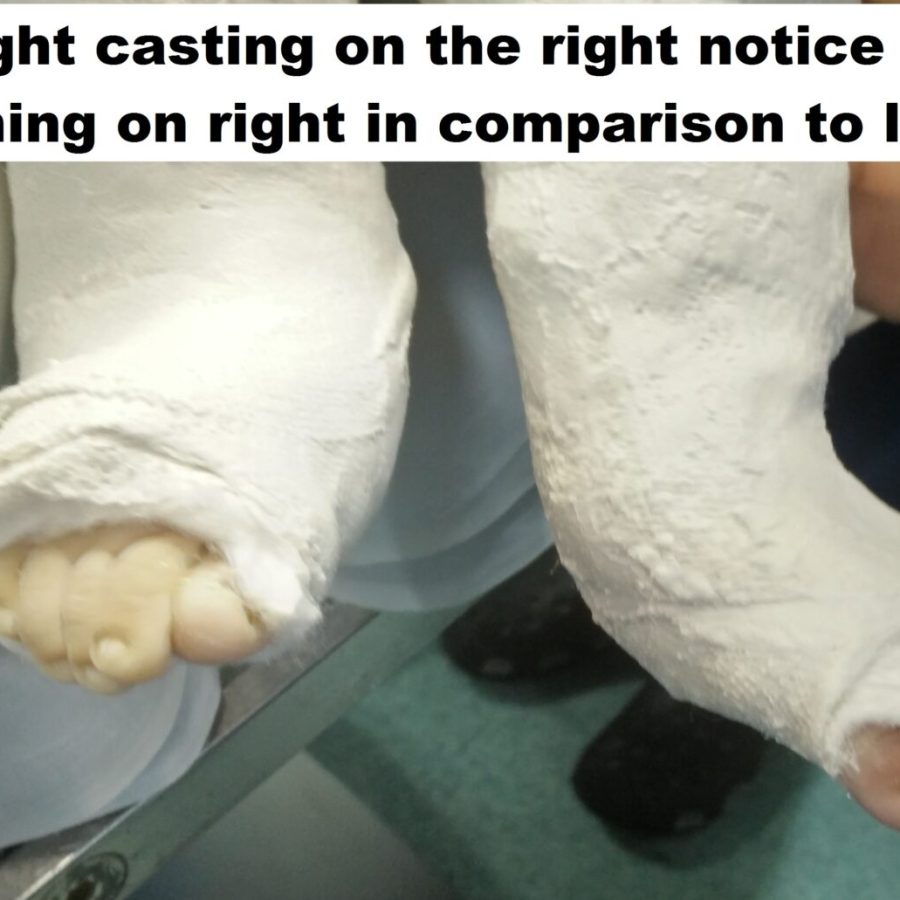

The serial POP casting of the feet weekly for 6-9 casts will help to obtain correction to most of the deformity except the equinus. In 80-90% of cases, the child needs a heel cord tenotomy to correct the deformity. We undertake the tenotomy in the operating room as there is complete control, and the child is relaxed. Many club foot kids do not have a dorsalis pedis artery. If there is an inadvertent injury to the posterior tibial artery during tenotomy, it can lead to significant problems of blood flow to the foot. Operating in the clinic has been advocated by Dr. Ponseti and has been done safely in large practices.

Post-tenotomy cast – 3 weeks

Bracing with Foot Abduction Orthosis- 22-23 hours for three months and later night time bracing for 3-4 years Dennis brown Splint/ Dobb’s splint are orthosis that helps maintain the correction of the deformity. The splints keep the affected foot in a 60-70 degree of external rotation and 20-30 degrees of dorsiflexion. The primary difference between the DB splint and the Dobb’s is the ability to move the feet independently in Dobb’s splint while both feet move together in Dennis Brown splint.